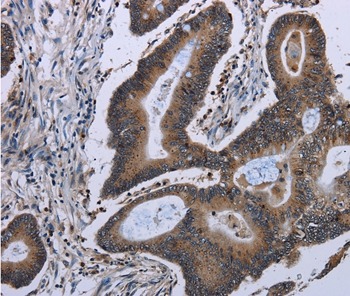

Immunohistochemical analysis of paraffin-embedded Human colon cancer tissue using #36557 at dilution 1/50.